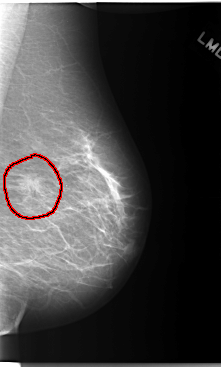

FILE: C_0103_1.LEFT_MLO.OVERLAY

TOTAL_ABNORMALITIES 1

ABNORMALITY 1

LESION_TYPE MASS SHAPE IRREGULAR MARGINS SPICULATED

ASSESSMENT 5

SUBTLETY 5

PATHOLOGY MALIGNANT

TOTAL_OUTLINES 1

BOUNDARY